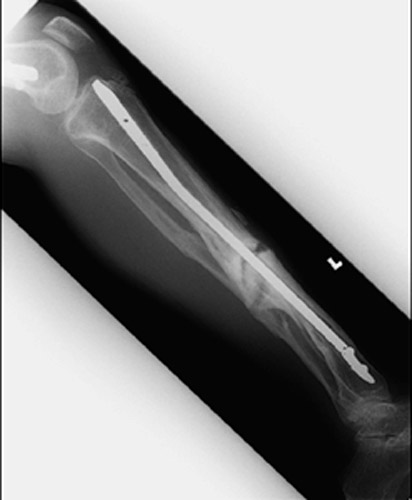

Return to Tibia and Fibula Fractures